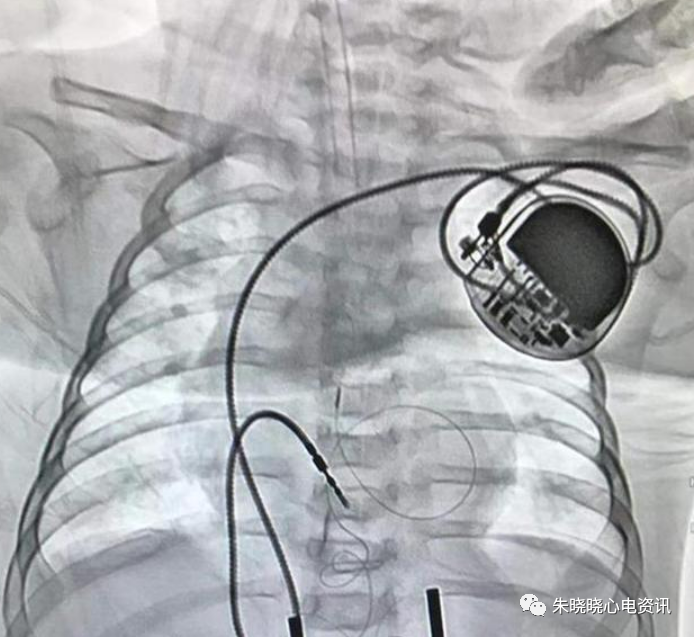

索林公司的Ela起搏器接线方式像杠铃(图13)

图13 索林公司ELA起搏器